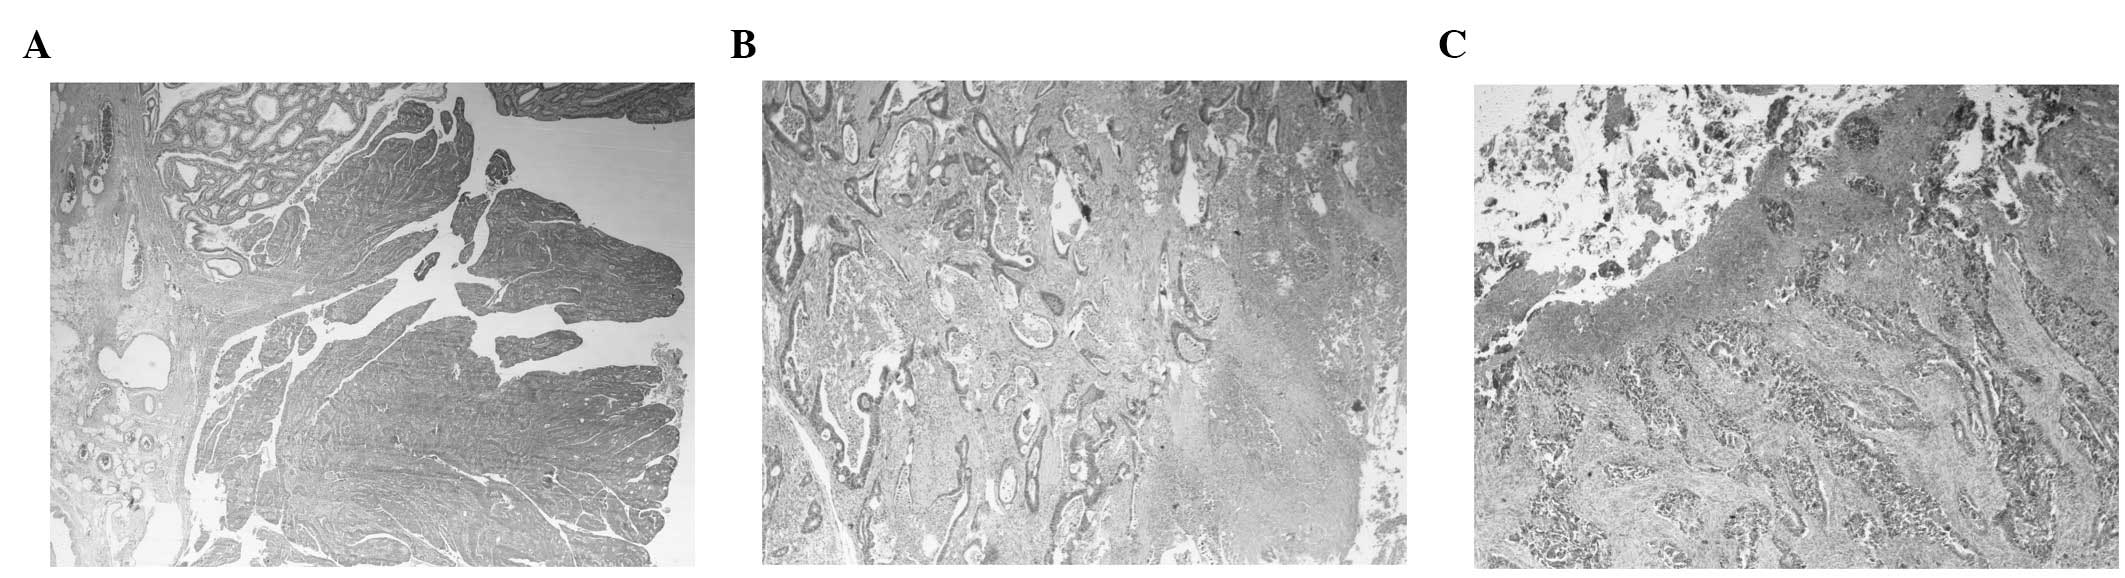

Table I shows the clinicopathological characteristics of the sample as well as the detection rates of the parameters investigated in this study. Adenomatous remnants were detected in 9 (7.5%), while coexisting polyps were observed in 11 cases (9.2%). The recorded frequencies of the exophytic and infiltrative (or ulceroinfiltrative) growth patterns were 20 and 32%, respectively. The remaining 48% of tumors exhibited a mixed or unclear growth pattern. Representative histologic images of lesions with remnants and of the various patterns are shown in Fig. 1.

Figure 1.

Histologic images (low power view) of (A) exophytic, (B) ulceroinfiltrative and (C) ulcerated adenocarcinomas. (A) Exophytic lesion accompanied by adenomatous remnant (magnification, ×20) is shown. (B) Ulceroinfiltrative tumor (magnification, ×40) is shown. (C) Ulcerated lesion (magnification, ×40) is shown.